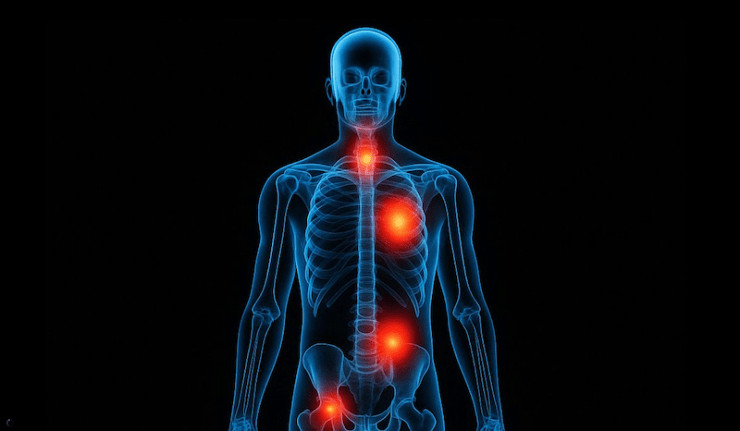

Ils ont injecté. Maintenant les corps parlent. 8,4 millions de patients. Une base de données nationale. Un pays sans Big Pharma. Juste les chiffres. Juste les morts.

Une étude publiée dans Biomarker Research révèle ce que des médecins courageux dénonçaient déjà à voix basse :

une explosion de cancers dans l'année qui suit la vaccination COVID. Pas des impressions. Pas des cas isolés. Des statistiques. Des corrélations. Des organes ciblés.

Les chiffres qui tuent le doute : 1 an après l'injection, +69% de risque de cancer de la prostate, +53% pour le poumon, +34% pour l'estomac, +35% pour la thyroïde, +28% pour le côlon et le rectum, +20% pour le sein.

Le mythe : «Les vaccins ne font que sauver». La réalité : une fraction de la population développe, dans les 12 mois, des tumeurs foudroyantes. Ces cancers ne sont pas normaux :

agressifs, jeunes, multiorganes, réfractaires